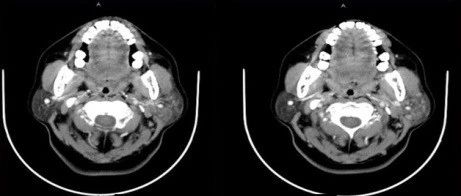

中年女性,左侧腮区反复肿胀1年余,请诊断!

感谢丁香达人 @米米兰妮 分享的病例:患儿:男性,13 岁。主诉:左侧颌面肿痛伴低热 1 天。查体:患儿左侧颌面部较右侧稍肿大,触诊包块边界不明显,触痛明显,皮温正常,无泼动感,张口受限。发病于冬春季节,考虑腮腺炎。完善血常规、超声检查,如下:超声提示:左侧腮腺未见明显异常。且超声老师明确说明是淋巴结肿大,不是腮腺炎症。血常规、CRP、SAS 均正常。本以为就等超声确诊,没想到可能误诊。诊断已出,一起加入讨论吧......